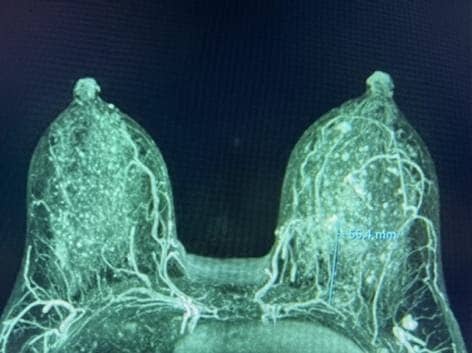

Figure 1. MRI MIP demonstrating the IMPs traveling to the NAC, superior to the nipple (left) and at the level of the nipple (right).

The breast MRI MIP (maximal intensity projection) images, a common reformat averaging multiple slices, clearly visualized the dominant blood supply to the NAC (Figure 1). Bilateral dominant IMPs, emanated from the pectoralis major muscle along the sternal border at the 2nd and/or 3rd intercostal spaces (ICS). Thereafter, the vessels coursed anteriorly in the subcutaneous tissue of the breast and terminated near the NAC.

The IMP-NSM surgical technique to preserve important NAC blood supply, has been previously published including the major important steps.1, 11, 12 Breast MRI with contrast, if obtained for preoperative staging, can clearly demonstrate the NAC blood supply, best visualized on MIP images. This shows the dominant NAC blood supply typically originating from the IMP bilaterally, usually at the 2nd or 3rd ICS along the sternal border (Figure 1).

The 2nd–4th ICS are marked on the skin, 1 cm lateral to the sternal border, indicating the common areas where the main IMP vessels are identified and preserved anterior to the pectoralis major muscle. The IMP-NSM technique can be performed without breast MRI, by marking these usual locations with subsequent careful dissection in those areas; however, if available, breast MRI images can provide helpful information regarding the IMP blood supply and anticipate the location at surgery. IMP-NSM is defined as preserving the dominant IMP blood supply to the NAC; however, the technique has evolved to include preserving additional small non-dominant IMP vessels visualized along the sternal border, which can contribute to vascular supply, in addition to associated ACN sensory branches. (Figures 1 and 2).